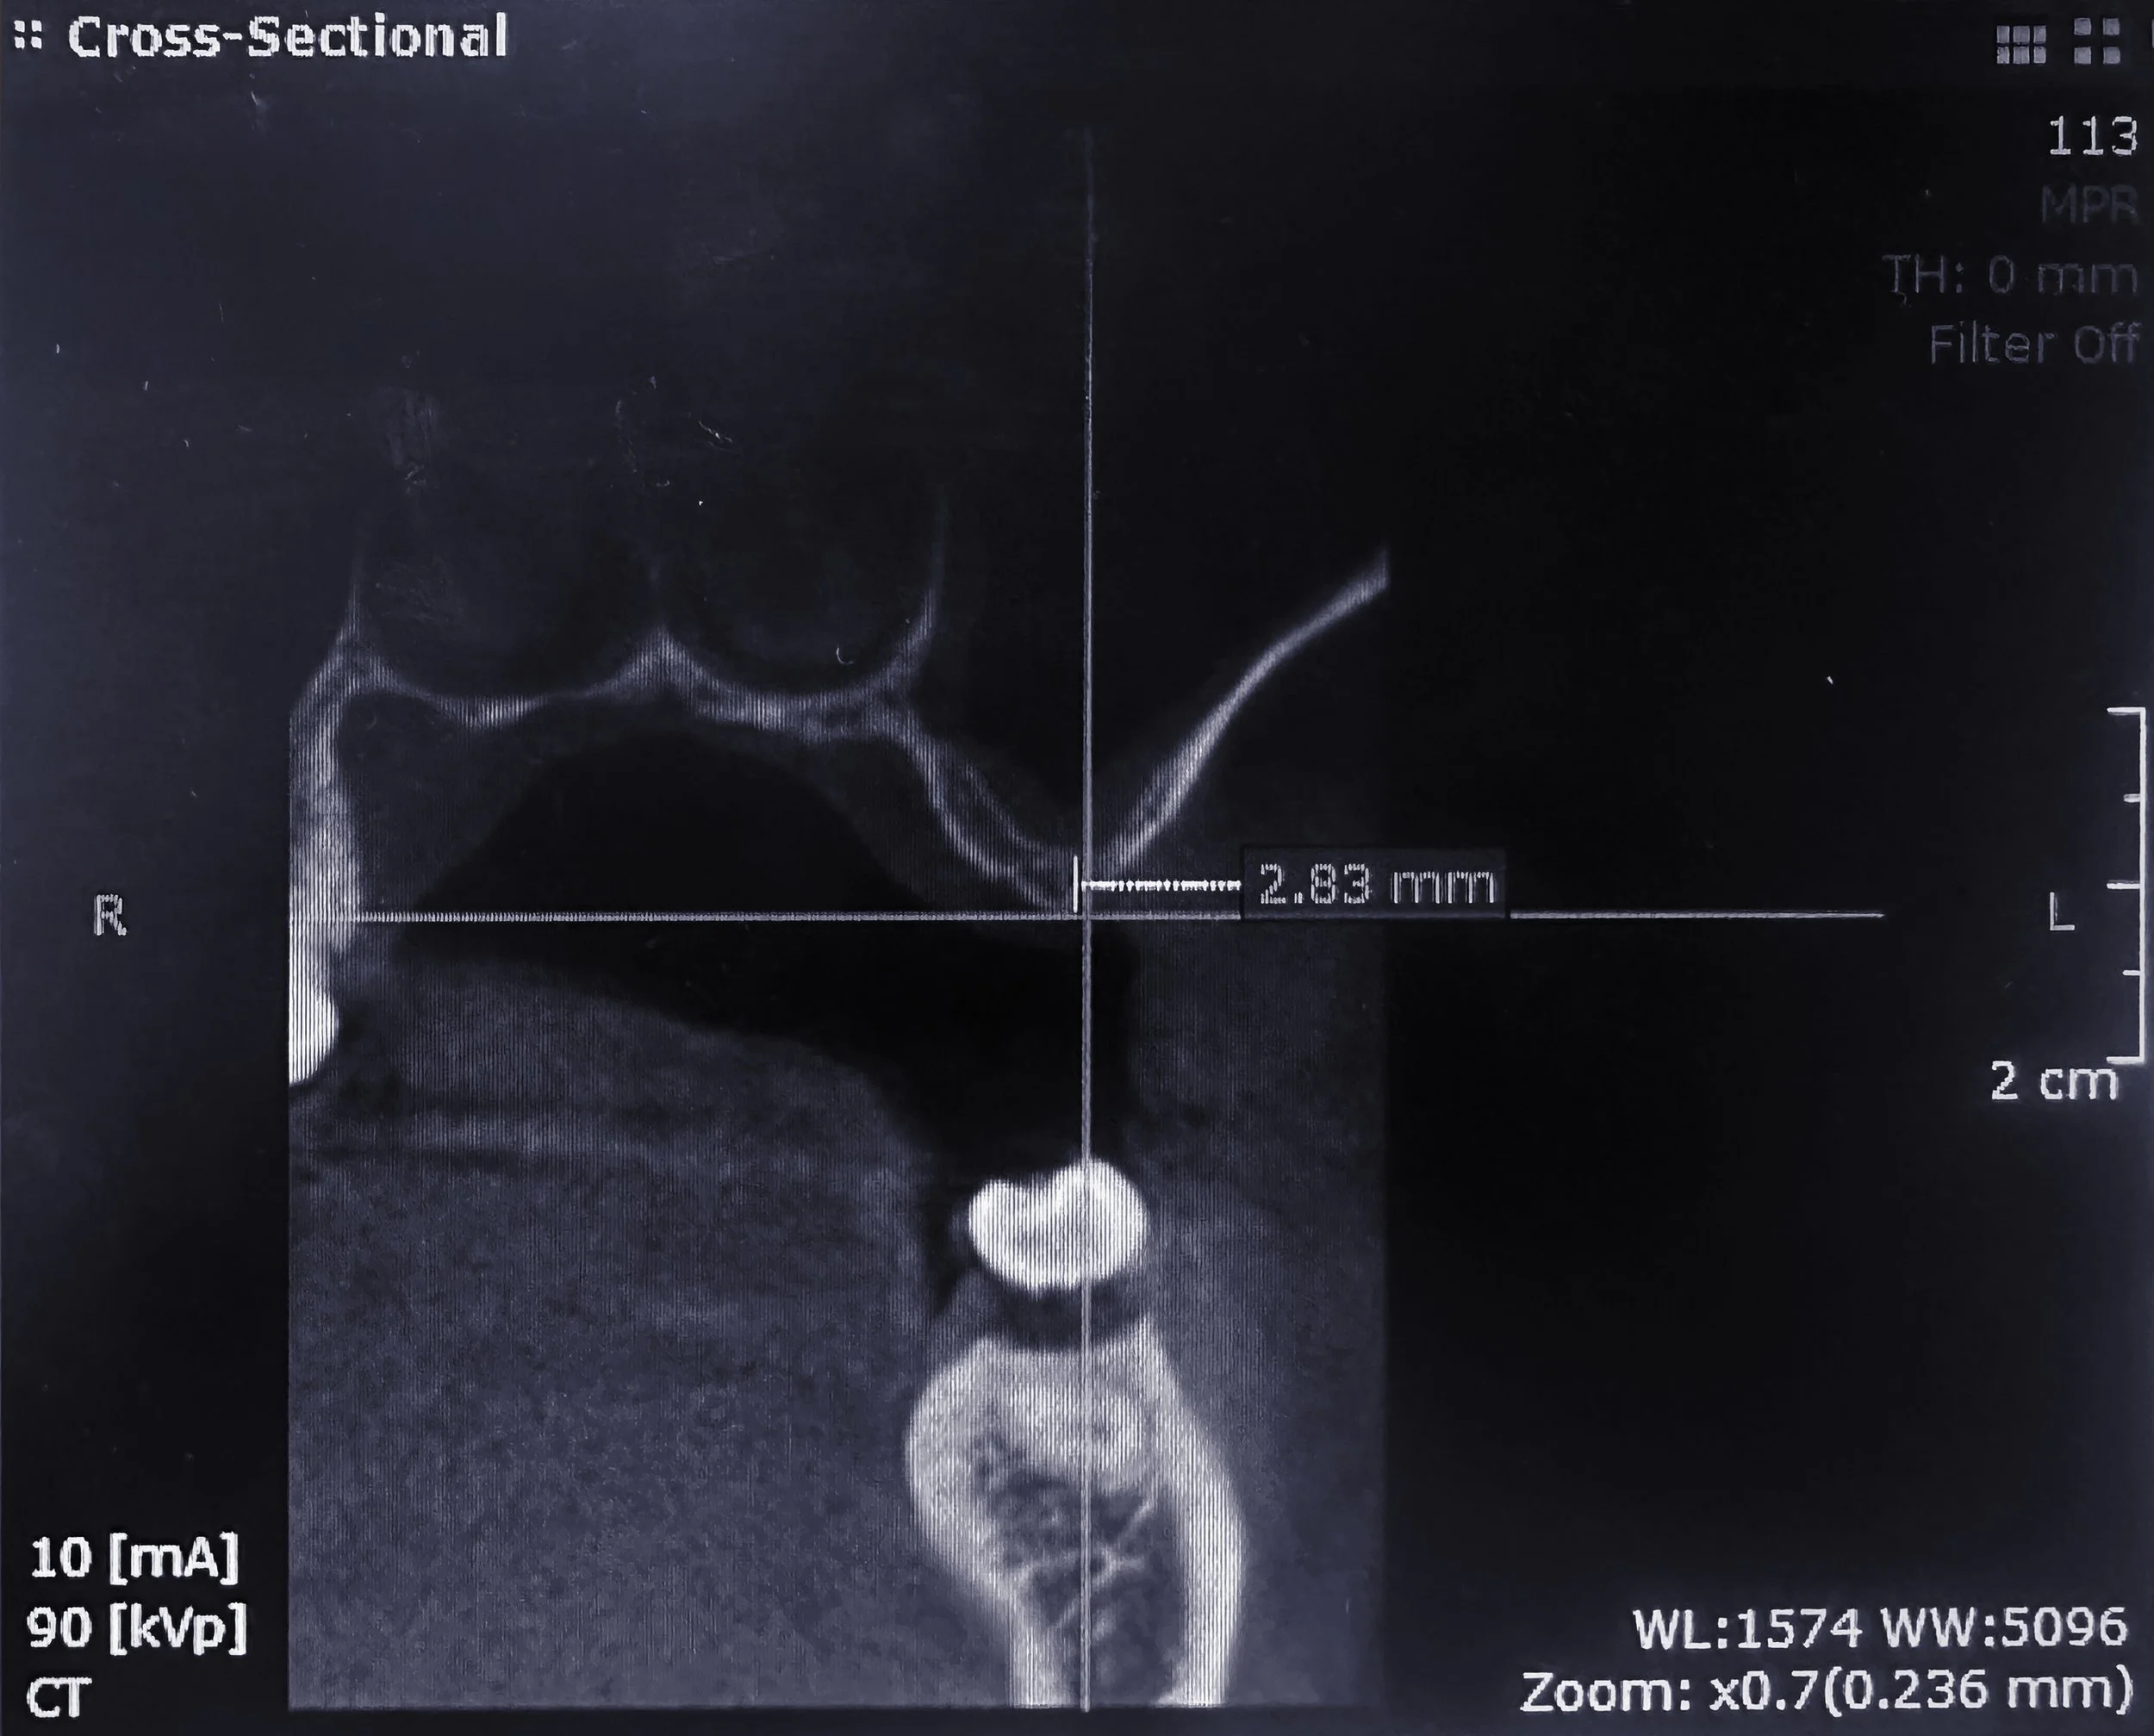

Case Highlight: #14 Surgical Extraction, Ridge Preservation, and Sinus Augmentation

Case Highlight: Lateral Window Sinus Lift — Tooth #14